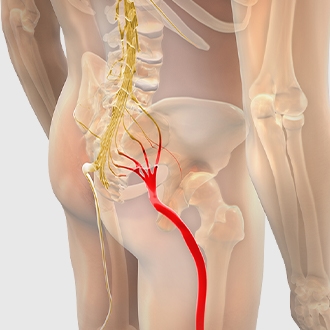

xem chi tiếtĐau thần kinh tọa

Triệu chứng đau, tê bì lan tỏa dọc theo đường đi của dây thần kinh tọa, từ thắt lưng qua hông và mông xuống bàn chân và thường chỉ xảy ra ở một bên cơ thể của người bệnh.